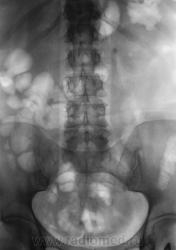

В голову лезут всякие бредовые идеи...и одна из них - инородное тело (суммация тени на тень почки) типа животной косточки.....Начинаю вновь "трясти" мужичка и...выплывает полный рот протезов и...."кушал кролика за сутки-двое до снимка" (на котором тень конкремента)....сомнения возрастают, тем более тень уж больно смахивает на короткую трубчастую кость из лапки мелкого животного (к примеру)......

Вызываю мужичка вновь из отделения и делаю прицельные снимки, в т.ч. с компрессией, левой почки....сомнения в наличии камня остаются...